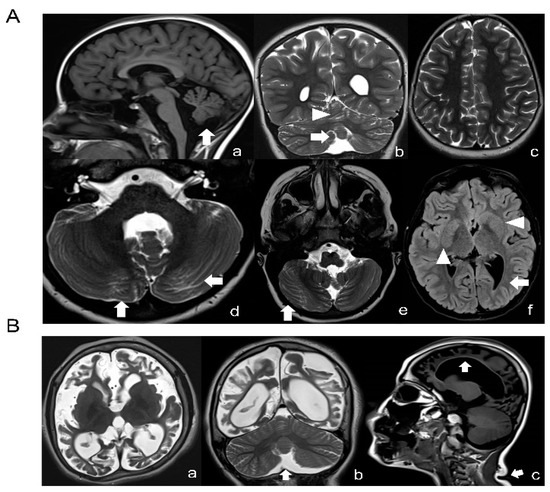

TUBB Variants Underlying Different Phenotypes Result in Altered Vesicle Trafficking and Microtubule Dynamics

Tubulinopathies are rare neurological disorders caused by alterations in tubulin structure and function, giving rise to a wide range of brain abnormalities involving neuronal proliferation, migration, differentiation and axon guidance. TUBB is one of the ten β-tubulin encoding genes present in the human [...] Read more.

Tubulinopathies are rare neurological disorders caused by alterations in tubulin structure and function, giving rise to a wide range of brain abnormalities involving neuronal proliferation, migration, differentiation and axon guidance. TUBB is one of the ten β-tubulin encoding genes present in the human genome and is broadly expressed in the developing central nervous system and the skin. Mutations in TUBB are responsible for two distinct pathological conditions: the first is characterized by microcephaly and complex structural brain malformations and the second, also known as “circumferential skin creases Kunze type” (CSC-KT), is associated to neurological features, excess skin folding and growth retardation. We used a combination of immunocytochemical and cellular approaches to explore, on patients’ derived fibroblasts, the functional consequences of two TUBB variants: the novel mutation (p.N52S), associated with basal ganglia and cerebellar dysgenesis, and the previously reported variant (p.M73T), linked to microcephaly, corpus callosum agenesis and CSC-KT skin phenotype. Our results demonstrate that these variants impair microtubule (MT) function and dynamics. Most importantly, our studies show an altered epidermal growth factor (EGF) and transferrin (Tf) intracellular vesicle trafficking in both patients’ fibroblasts, suggesting a specific role of TUBB in MT-dependent vesicular transport. Full article